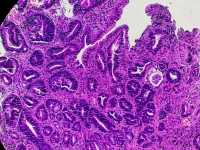

男66岁胃窦剥脱样糜烂

慢性萎缩性胃炎伴肠化、糜烂。可见修复性改变。